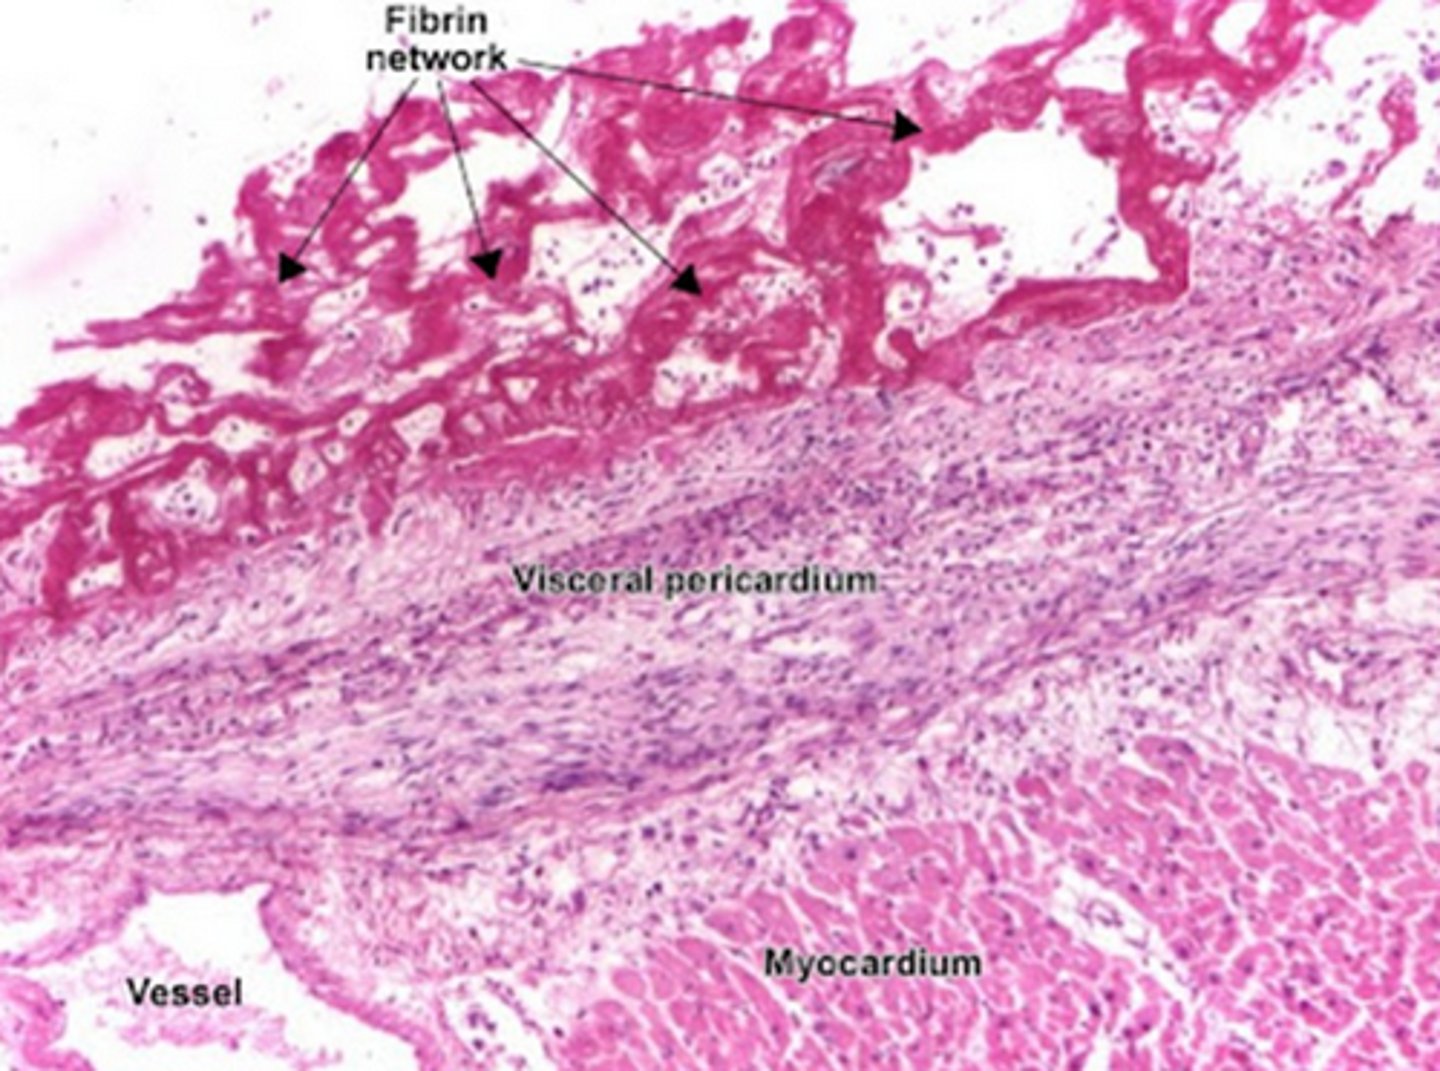

Chest pain, pericardial effusion/friction rub, persistent fever following MI (weeks later)

Dressler syndrome

(autoimmune mediated post-MI fibrinous pericarditis, 2-12 weeks after acute episode)